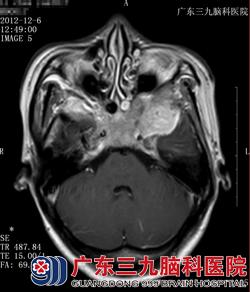

图一 图二

图一、图二:CT:颅底骨质呈骨性破坏,左侧中颅底示云雾状瘤骨。